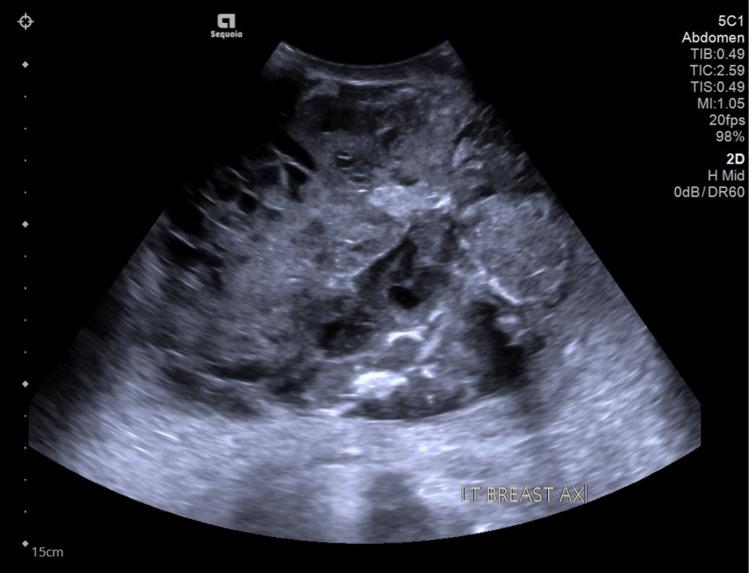

Carcinosarcoma of the breast is a subtype of metaplastic breast carcinoma characterized by differentiation of the neoplastic epithelium toward mesenchymal-looking elements. It is a highly aggressive rare subtype of invasive breast neoplasm that exhibits a distinct histologic entity. Only a limited number of reports related to this type of disease have been reported. Here, we present a case of breast carcinosarcoma in a lady in her early 20s, which is relatively young among all cases published. It was challenging to achieve diagnosis preoperatively with histopathological evaluation of the ultrasound-guided tru-cut biopsy sample. With no evidence of distant metastasis clinically and radiologically, a surgical option was opted for. Left mastectomy and left chest wall reconstruction with deep inferior epigastric artery free flap were performed. Post-excision specimen was confirmed to be carcinosarcoma.